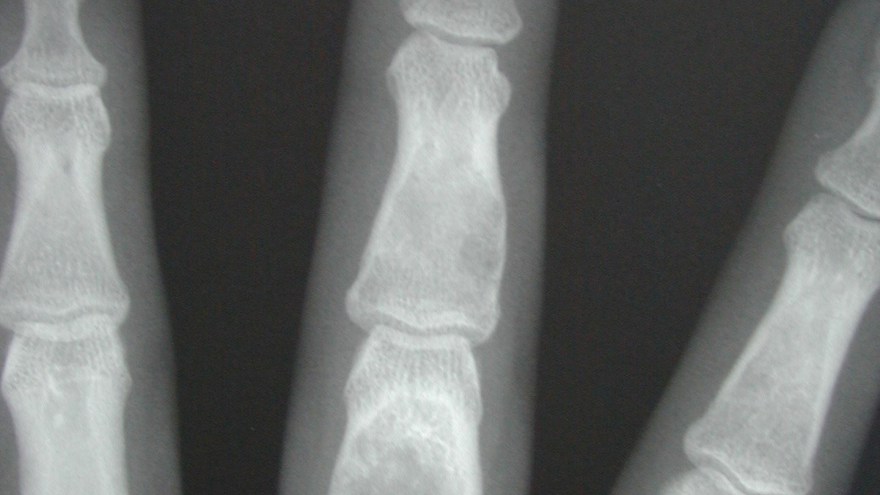

Enchondrom